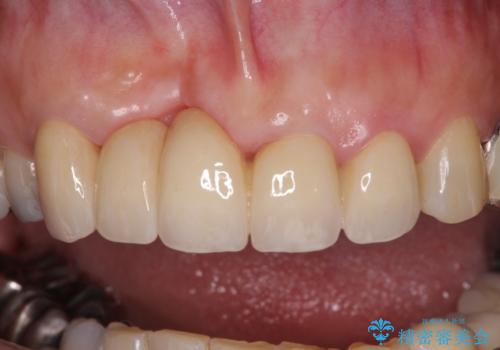

仮歯に置き換えた時点で見た目が大きく改善され、人目を気にすることがなくなりました。

オールセラミッククラウンは、本物の歯のような外観となり、患者様には大変満足していただけました。